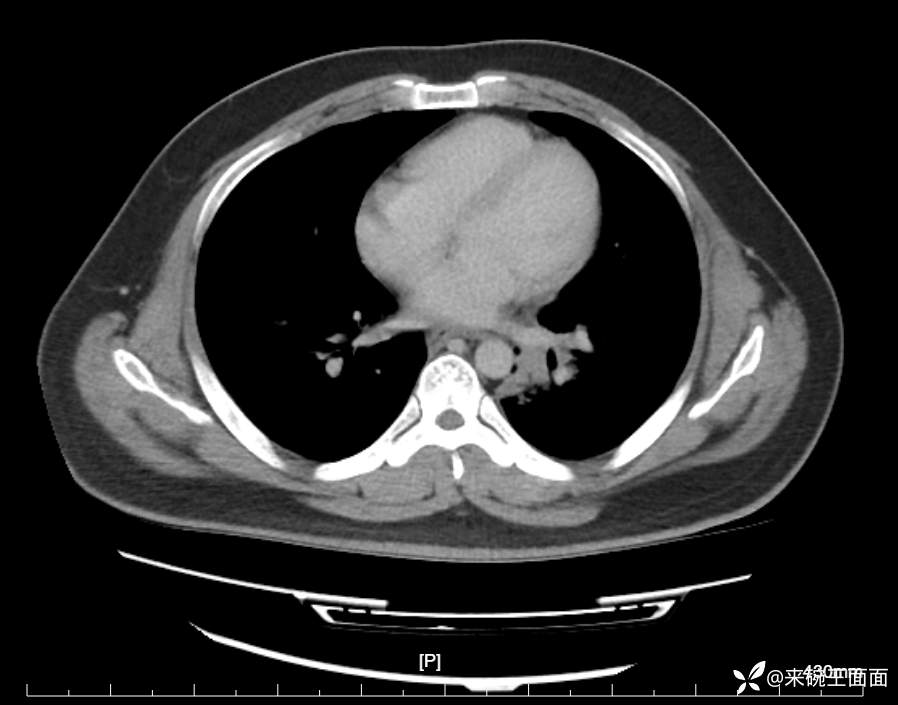

性别:男

年龄:27岁

主诉:胸闷胸痛数月余,休息后可自行缓解,无咯血症状。

个人史:数年吸烟史,具体不详。